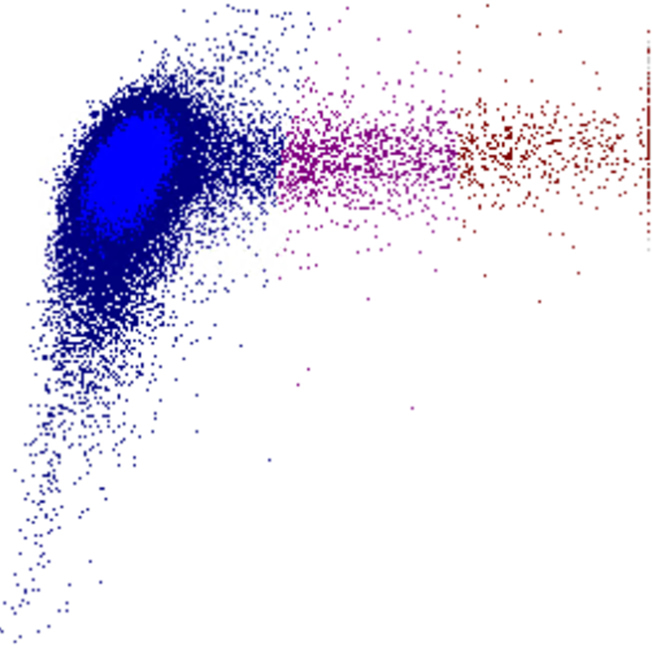

Densité

La densité des points dans un diagramme de dispersion reflète le nombre de cellules présentant des caractéristiques physiques et de fluorescence similaires. Le diagramme indique ainsi non seulement la présence de populations cellulaires, mais aussi leur taille relative et leur homogénéité.

• Une forte densité de points indique une population cellulaire importante et relativement homogène

• Des motifs diffus ou dispersés peuvent suggérer une hétérogénéité, une activation ou la présence de cellules anormales

• Des déplacements, un élargissement ou un chevauchement entre populations constituent souvent des signes précoces de morphologie anormale ou de cellules rares